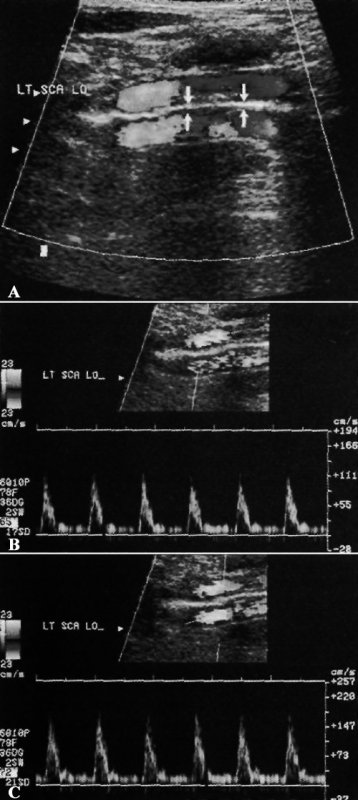

При допплерографии артефакт зеркального изображения такой же, как и при ультразвуковом исследовании в режиме серой шкалы (см статью «Основы УЗИ: Артефакты в режиме серой шкалы»). Мощный зеркальный рефлектор отражает допплеровский сигнал к объекту и обратно, при этом увеличивается время возврата волны к датчику. Во время допплеровского исследования волны отражаются, как правило, от поверхности плевры, при этом наблюдается зеркальное отражение подключичной артерии или вены. Спектральный допплеровский сигнал отражается аналогично цветной допплерографии (фото 9).

Допплерография подключичной артерии: артефакт зеркального изображения

Фото 9. Допплерография подключичной артерии: артефакт зеркального изображения. А – на допплерограмме визуализируется нормальная подключичная артерия, при этом наблюдается вторая аналогичная артерия под поверхностью плевры (см стрелки). В – спектральный допплеровский сигнал истинной артерии не отличается от сигнала отраженной (зеркальной) артерии (фото С)